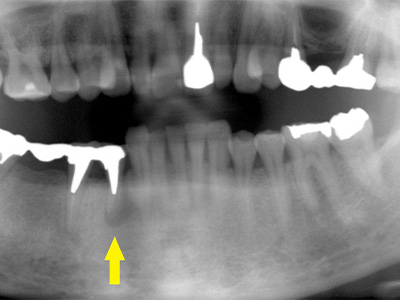

患者様は50代男性。インプラント治療前のレントゲン写真です。

右下顎大臼歯2本の抜歯後のレントゲン写真で、写真の黄色矢印は、歯の周囲の歯槽骨が大きく吸収されてしまっていました(黄色矢印)。 -